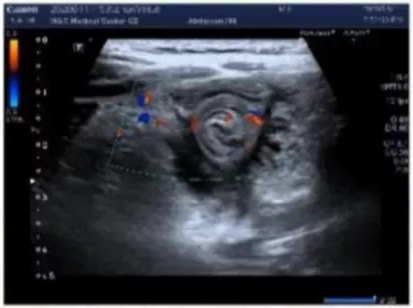

總之,面對腹痛患兒,首先應當根據患兒腹痛的特征,判斷出是急腹癥(腹痛持續,陽性腹征固定),又或是非急腹癥(間歇腹痛,無固定腹征),之后再根據進一步的檢查鑒別診斷。圖.小兒腹痛診斷思路/圖片來源耿嵐嵐教授PPT截圖當患兒腹痛持續6小時以上,腹部局部體征為壓痛、肌緊張、腫物、腸型;同時,以上各項具有固定的位置、固定的范圍、固定的性質,多次檢查不變,就是典型的急腹癥了。1、局部炎癥類:按照壓痛的位置可作出判斷,如闌尾炎、膽囊炎、胰腺炎、卵巢扭轉。這其中,有一些急性腹痛可能需要手術的征象,一定要注意識別,包括:無腸鳴音、膽汁性嘔吐、血性腹瀉或大便潛血、發熱≥38°C、反跳痛、肌緊張、自主性肌衛等。患兒出現的癥狀越多,越提示存在急腹癥。8、功能性腹痛:嬰兒腸絞痛、功能性消化不良、腹型偏頭痛、腸易激綜合征、功能性腹痛-未定型因此,進一步的實驗室檢查與影像學檢查,是免不了的。它們可以幫助醫生更好地鑒別腹痛病因。在影像學檢查中,腹部超聲與X光片是常用的兩大類檢查方式。超聲對兒童常見急腹癥的診斷準確率較高,能夠較好的指導臨床治療,且具有方便、迅速、廉價、無痛、無輻射等優點,是兒童急腹癥首選的影像學檢查。表2.小兒急腹癥常見病大多在超聲下有相應的特征性表現

體檢:腹軟,右下腹壓痛明顯,未捫及明顯包塊。肛門指檢:退指可見大便排出,未見血便。面對這樣一個患兒,你會考慮哪些腹痛病因?下一步做什么檢查?進一步超聲檢查發現:右下腹探及一混合回聲包塊,范圍約28×23×19mm,呈異常形態腸管樣。考慮:右下腹炎性包塊——Meckel憩室可能、腹腔局部積膿。最后,手術和病理確診Meckel憩室合并化膿性炎癥。本文來源:醫學界兒科頻道